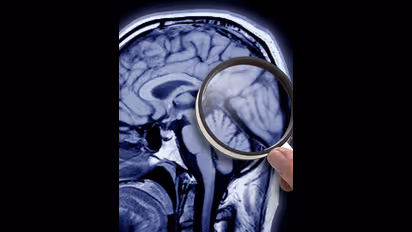

അല്ഷിമേഴ്സ് രോഗത്തെ കുറിച്ച് ഇന്ന് ധാരാളം പേര്ക്ക് അവബോധമുള്ളതാണ്. നമ്മുടെ തലച്ചോറിനെ ബാധിക്കുന്നൊരു രോഗമാണിത്. പ്രധാനമായും മറവിയാണ് അല്ഷിമേഴ്സ് രോഗത്തിന്റെ വലിയൊരു പ്രശ്നം. പതിയെ പതിയെ ആയി രോഗി എല്ലാം മറന്നുപോകുന്ന അവസ്ഥയാണ് അല്ഷിമേഴ്സിന്റെ ഏറ്റവും വലിയ വെല്ലുവിളി.

അല്ഷിമേഴ്സ് രോഗികളില് രോഗത്തിന് കാരണമായി വരുന്ന അമൈലോയിഡ് എന്ന പ്രോട്ടീനിനെയാണ് 'Donanemab' മരുന്ന് ലക്ഷ്യമിടുകയത്രേ. ഇങ്ങനെ രോഗിയുടെ തലച്ചോറില് രോഗം പടര്ന്നുകയറുന്നത് അങ്ങേയറ്റം മന്ദഗതിയിലാക്കാനാണ് മരുന്ന് ശ്രമിക്കുക.